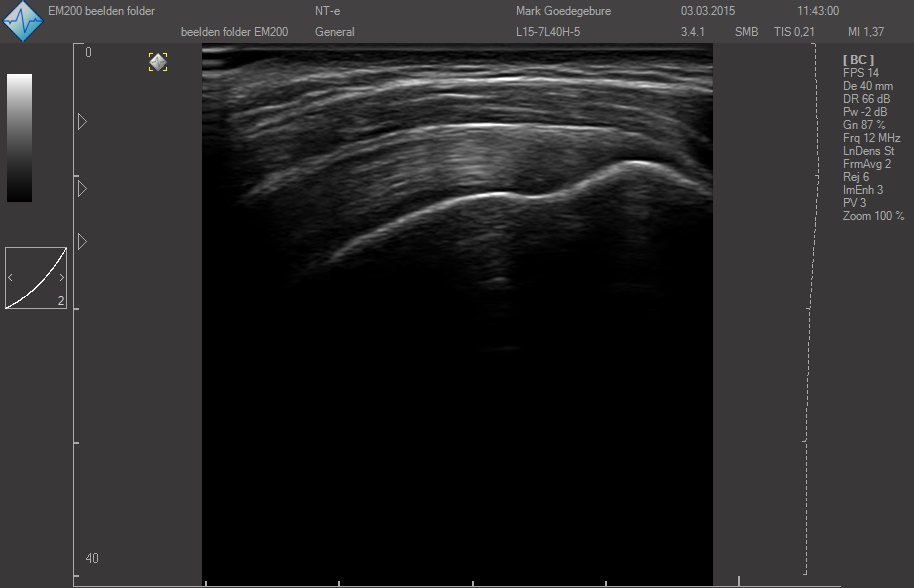

Датчики имеют большую чувствительность и высокое разрешение, благодаря чему обеспечивают максимальное проникновение и улучшают соотношение сигнал /шум. В результате формируется максимально четкая детализированная картинка УЗИ изображения.

ЗДЕСЬ Вы можете посмотреть реальные кинопетли с аппарата УЗИ SmartUs.